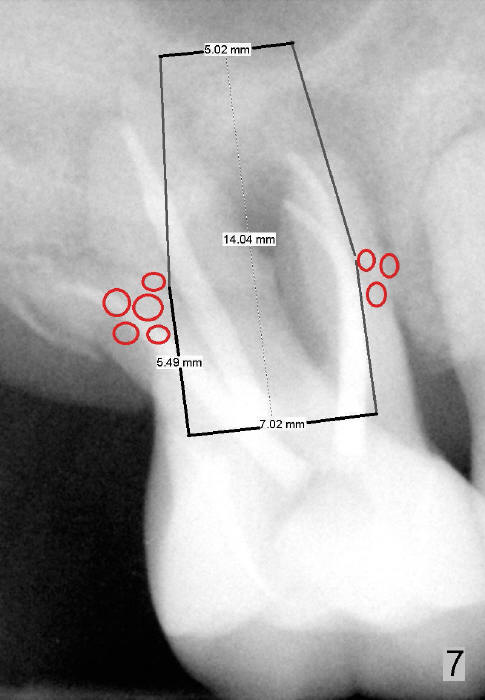

If primary stability is questionable with the bone-level implants mentioned above, a 7x14 mm gingiva-level implant will be the next alternative (Fig.7).  If primary stability is still insufficient, a 7x17 mm (with sinus lift) or 8x14 or 17 mm will be placed (Fig.8).  The larger the implant, the less bone graft is used (compare Fig.7,8).